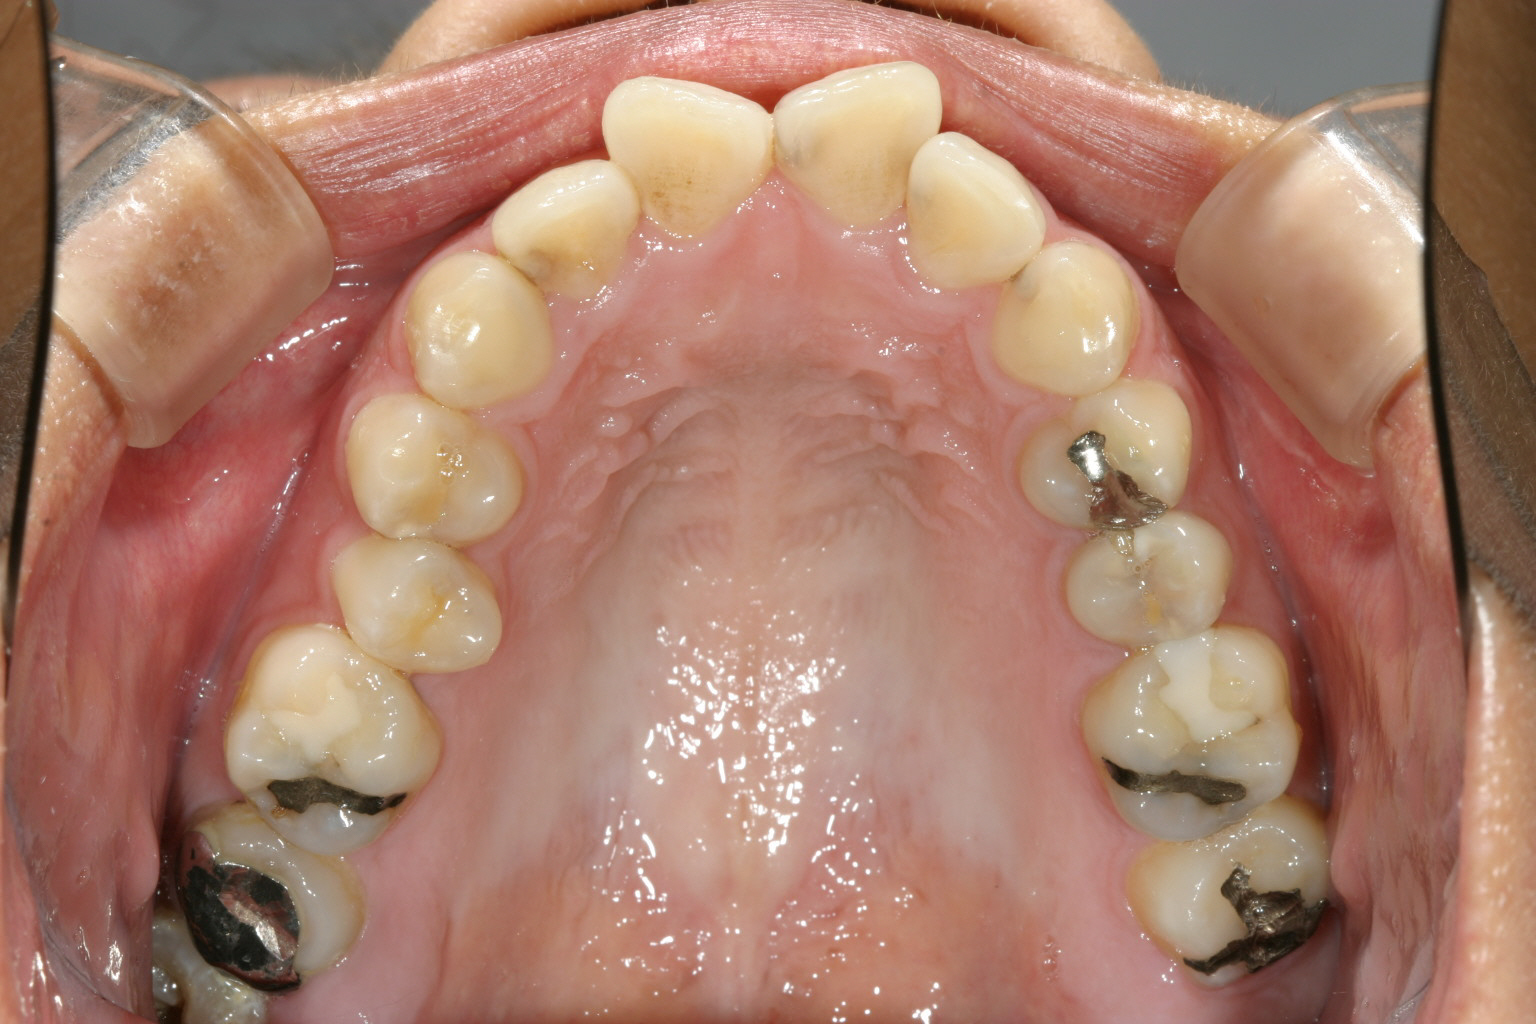

典型的な翼状捻転です。 アーチが狭いですね~

今回のケースはアーチが狭いのが原因で起きる典型的な翼状捻転です。